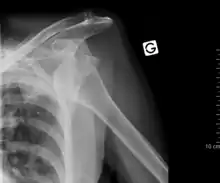

An anterior dislocation of the shoulder

Anterior dislocation of the right shoulder. Y view X ray.